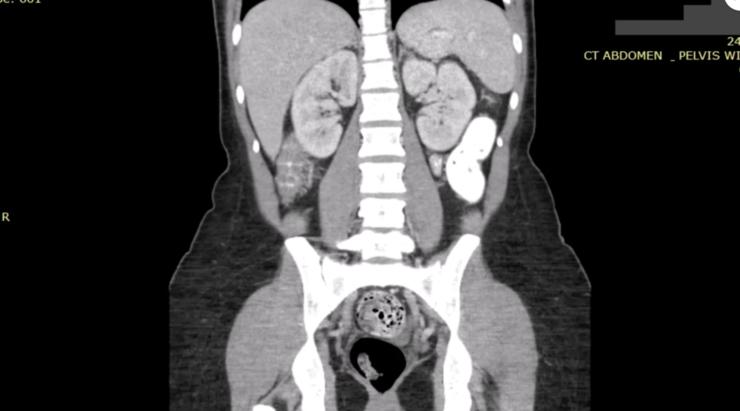

不过,有一种“坦诚相见”的场景你可能更没想到过。你刚进医院拍了一张 CT 。嘿,影像副本可能流到了黑客手里。

每天,数以百万计包含病人个人健康信息的新医学图像都在互联网上流传。

倒也不是别人费了九牛二虎之力去偷的,可怕的是,这些医院、医疗办公室和成像中心的“门”并没有关好。它们正在使用不安全的存储系统,只要有互联网连接,任何人都可以访问超过 10 亿张病人的医学图像。

虽然,现在大约一半被暴露于互联网的图像,包括 x 射线、超声波和 CT 扫描的图片都来自正在和伊朗闹得不可开交的美国,但这并不代表中国的医院能置身事外。

你要说了,这些医院影像头像又看不出实际上是谁,没有暴露隐私。其实不是的,这些未受保护的服务器不仅暴露医疗成像,而且暴露了病人的个人健康信息。

许多扫描图像不仅有 DICOM 文件的封面,还有病人的姓名、出生日期和有关他们诊断的敏感信息,甚至还有他们的社保 ID。

比如,一个真实案例是,一位患有慢性病的患者在加利福尼亚的一家医院进行了长达 30 年的定期扫描,他的医学图像一经暴露,30 年的健康状况一览无余,而 美国最大的军事医院之一一个未受保护的服务器也暴露了军事人员的名字和医学图像。

即使病人只有一张或几张医学图像,暴露的数据也可以用来推断一个人的健康状况,包括罹患的疾病和受到的伤害。